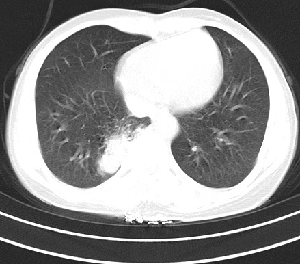

下叶后基底段近膈面见一椭圆形密度均匀增高的阴影,边界较清,其长轴指向内后方,考虑肺隔离症,建议增强扫描了解与主a联系!

右下肺隔离症有可能,另外可能是炎性假瘤

右下肺隔离症考虑,不除外炎性假瘤,建议增强。

右下肺隔离症可能性大,不除外炎性假瘤,建议增强。

右下肺隔离症可能性大,不除外炎性假瘤、神经原性肿瘤